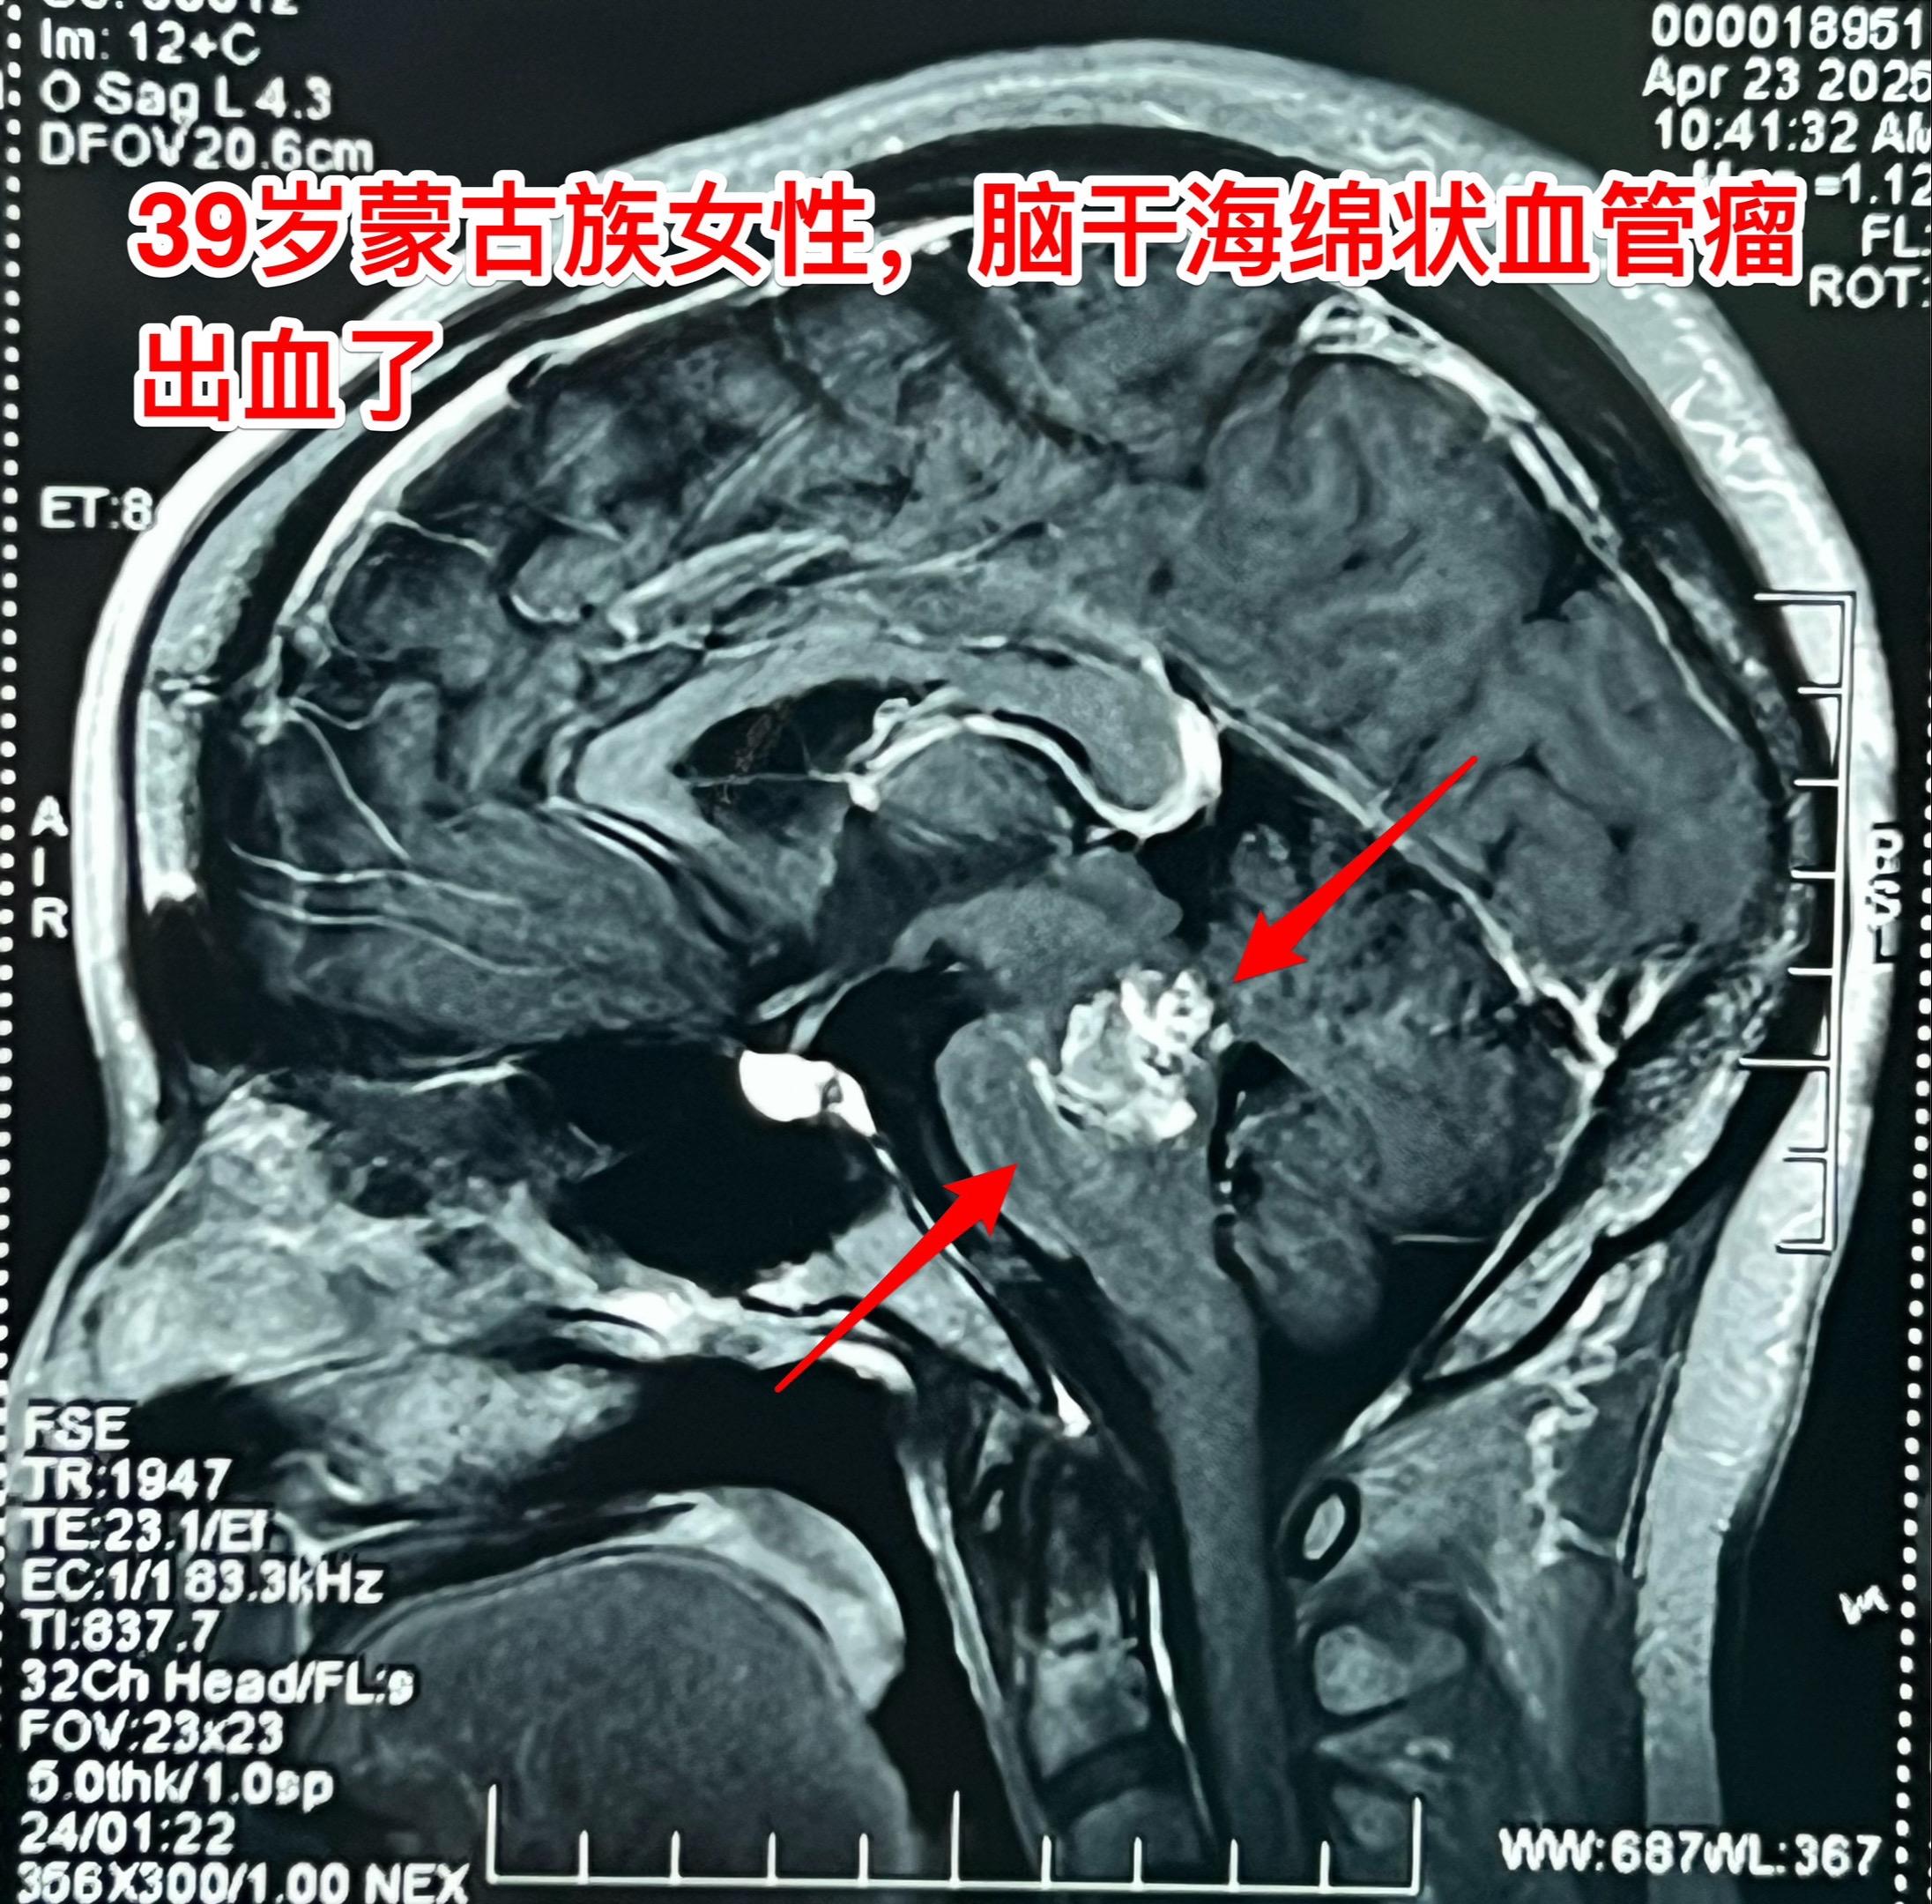

脑干海绵状血管瘤两次出血了—应该切除掉。39岁的蒙古族女性生活在内蒙古赤峰市的农业区,不过是真正的蒙古人。 近两年间断两次出现身体发麻。两年前曾经作 磁共振检查发现了脑干出血, 出血原因是海绵状血管瘤自发破裂。近期再次出现身体发麻,到医院检查发现脑干海绵状血管瘤再次出血了!如图所示,海绵状血管瘤直接大约2厘米,比两年前体积增大了,而且再次出血了。 这样的海绵状血管瘤就该作手术切除掉!尽管这个部位的手术难度很大。如果不作手术则很有可能再次出血,甚至导致病人昏迷或者成为植物人。